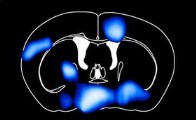

الکساندر جیس،نویسنده این پژوهش اظهار کرد: یک رژیم غذایی با چربی بالا در کمتر از سه روز میتواند جذب قند خون را کاهش داده و سبب گرسنگی مغز شود. حتی اگر موشها روزانه مقدار زیادی کالری مصرف کنند. مسئول این امر پروتئین GLUT-1 است، که مهمترین ناقل گلوکز در سد خونی مغزی است. عوامل ممکن برای کاهش GLUT-1 ، اسیدهای چرب اشباع شده هستند که دارای اثر سمی بر روی سلولهای سد خونی مغزی هستند. در نتیجه مغز قند خود را در مناطق قابل توجهی مانند هیپوتالاموس از دست میدهد که کنترل سوخت و ساز بدن و قشر مغز را بر عهده داشته و مسئول یادگیری و حافظه است.

پس از آن،مغز برای جبران فقدان انرژی اقدام کرده و ماکروفاژها که سلولهای تخصصی در سیستم ایمنی بدن هستند، فاکتور رشد VEGF که باعث افزایش تولید و عملکرد GLUT-1می شود را تولید کرده و آن را به طور مستقیم در سلولهای آندوتلیال عروقی در سد خونی مغز منتشر میکنند.

پس از گذشت چهار هفته حتی اگر موشها همچنان به خوردن یک رژیم غذایی با چربی بالا ادامه دهند، می توان وجود قند خون نرمال را در مغز مشاهده کرد. اگر موش ها فاقد فاکتور رشد VEGF باشند، جذب گلوکز در مغز در سطح پایین باقی مانده و در نتیجه سبب اختلال حافظه در موشها و کند شدن روند یادگیری آنها می شود.